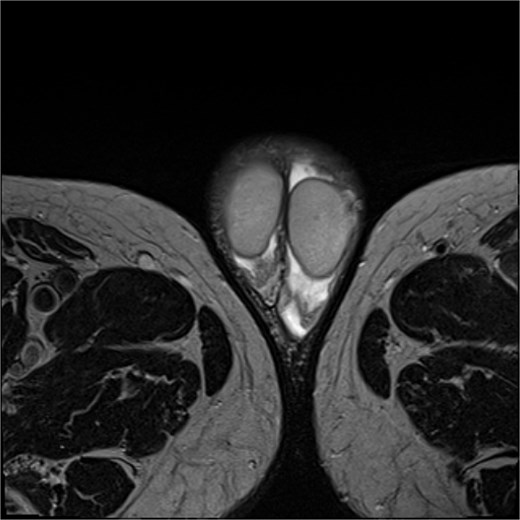

Physical examination revealed multiple subcentimetric brown-to-black elevated lesions with irregular, poorly defined margins and widespread ulcerations, involving the scrotum, the base and shaft of the penis, and the adjacent genital skin. Marked lymphedema of the entire penile shaft was observed, likely secondary to previous surgical resections. Partially obscured by the edema, an extensive ulcerated lesion of the glans was also noted. No adherence to underlying tissues or palpable lymphadenopathy in the bilateral inguinal regions was detected (Fig. 1). A magnetic resonance image (MRI) revealed an absence of infiltration in the corpora cavernosa, urethra, and testicles (Fig. 2). Flexible cystoscopy showed no urethral strictures. Despite the severity of the disease, erectile function was not seriously compromised (IIEF-5 score: 18); however, the patient reported substantial sexual discomfort due to the lesions and penile swelling, resulting in a significant reduction in his quality of life (QoL).